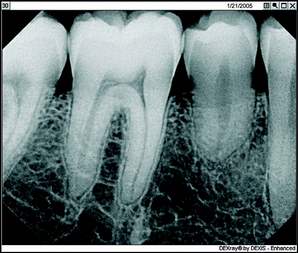

Top: Image Enchancement using ClearVU

First, there's the critical matter of diagnostic capability. I don't care what other dentists might say who are still trying to convince themselves they should stick with film technology, you can improve your diagnostic capability significantly using digital radiography. With digital, you're looking at an image that fills a 19-inch computer screen and not a film image the size of a postage stamp. Using the software-based digital radiography's image enhancement functions such as magnification, brightness control, and heightened contrast, you can bring out aspects of the X-ray that simply aren't visible on film, including such things as tiny fractures and imperfections that you might very well miss on film. Once you begin to practice using magnification for vision, you wouldn’t practice without it. It’s the same with the digital x-rays.